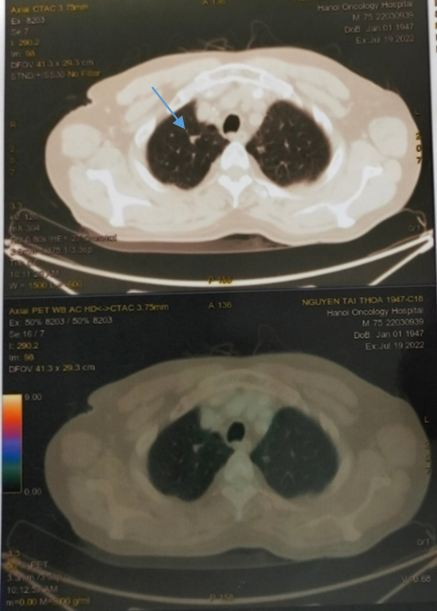

- Vài nốt mờ nhu mô phổi hai bên, tăng nhẹ chuyển hóa FDG – khả năng do di căn

Hình ảnh CT (phía trên) và PET/CT (phía dưới)  thấy các nốt nhu mô phổi phải có tăng nhẹ chuyển hóa FDG